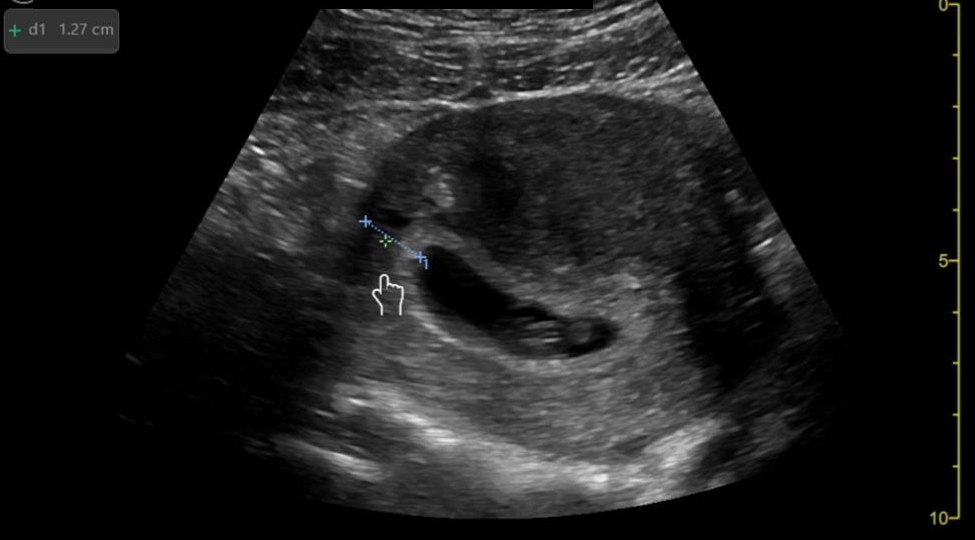

Image 1: Intussusception short axis diameter measurements.